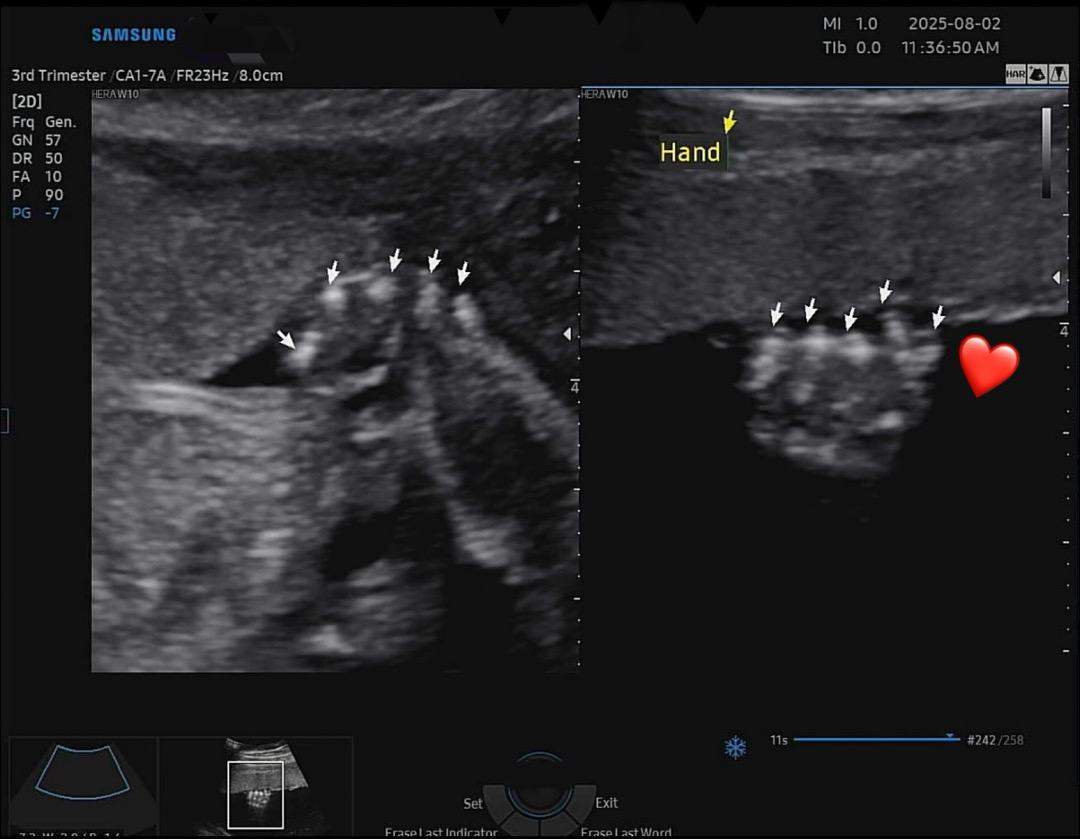

주말에 정밀초음파검사 보고왔는데 손가락 확인할때 애기가 귀엽게 손가락하트를 해주더라고요!!😆 주책이지만 너무 귀여운 순간이라 공유해봅니다🥰